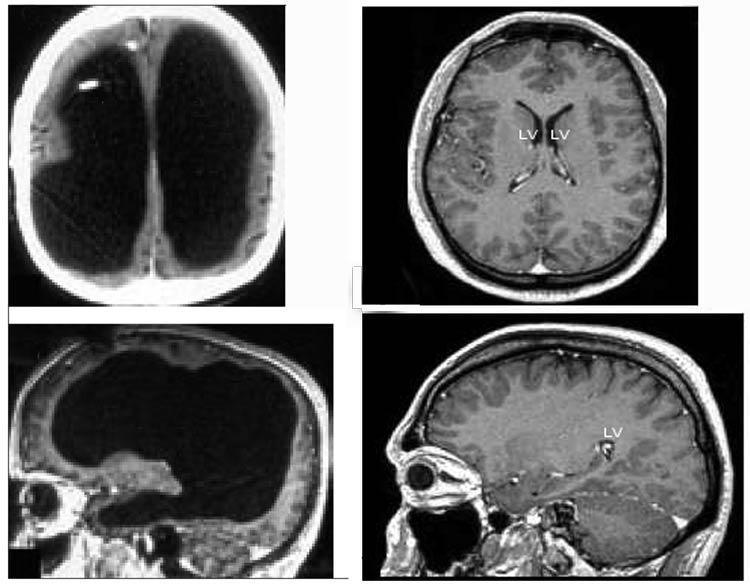

Магнитно-резонансная томограмма пациента с практически отсутствующим мозгом, но ведущим нормальную социальную жизнь. Фото: Feuillet et al./The Lancet

На иллюстрации слева показана томограмма мозга пациента, у которого большая часть черепа заполнена жидкостью. Для сравнения, на томограмме справа — через обычного мозга без аномалий.